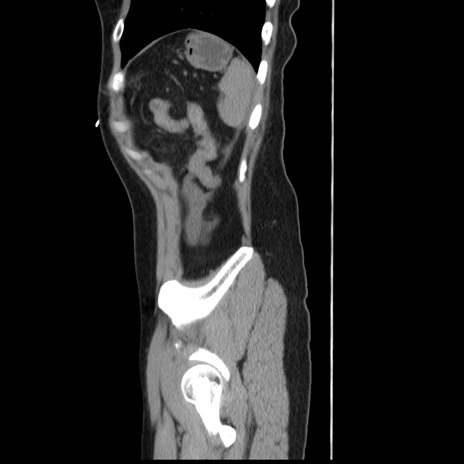

症例10(矢状断像)

【症例】 50歳代女性

【主訴】 腹痛

【現病歴】前日生レバーを食べた。今朝に排便あり。 昼前に突然発症の腹痛を生じ、当院救急外来を受診した。

【既往歴】 子宮筋腫にてで子宮全摘後

【身体所見】 意識清明、腹部:平坦、軟、下腹部やや左を中心に圧痛・反跳痛あり、筋性防御あり

【データ】WBC 7800、CRP 0.07